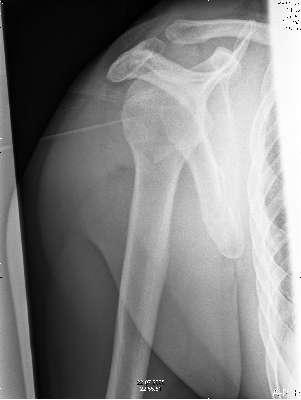

Maar op 9 augustus bleek dan niet zo te zijn en moest er de volgende dag geopereerd worden. |